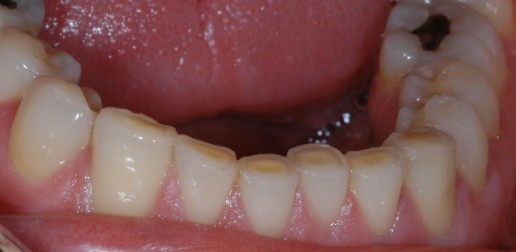

Grincer et/ou serrer fréquemment les dents les use prématurément. Des facettes d’usure commencent par apparaitre sur l’émail. Puis, à mesure que l’abrasion se poursuit, l’émail se perfore par endroit laissant le corps de la dent (la dentine) sans protection. La dentine est d’aspect plus jaune, et est beaucoup moins résistant à l’usure que l’émail.

Pour préserver les dents il est alors conseiller de porter la nuit une « gouttière de bruxisme » faite sur mesure. Les dents useront la gouttière mais ne s’useront pas entre elles.